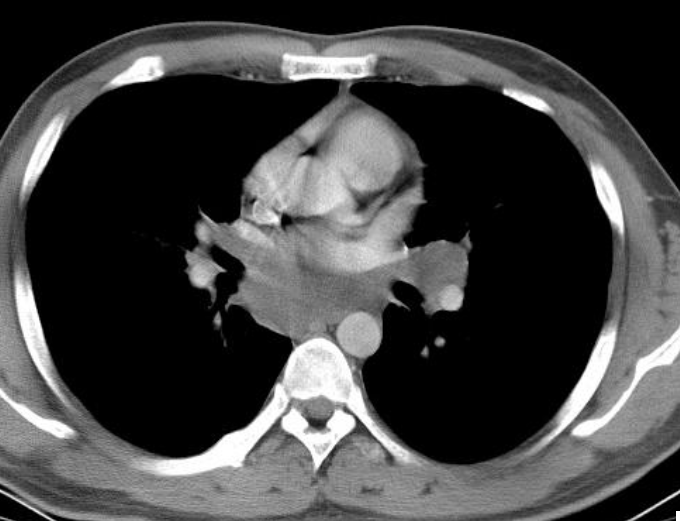

2. 血行播散性肺结核:急性血行播散性肺结核表现为两肺均匀分布的大小、密度一致的粟粒阴影;亚急性或慢性血行播散性肺结核的弥漫病灶,多分布于两肺的上中部,大小不一,密度不等,可有融合。需与电焊工尘肺、肺转移瘤等其他疾病鉴别。

*血行播散性肺结核:均匀分布的大小、密度一致的粟粒结节

*误诊为血播肺结核的电焊工尘肺,弥漫性肺病都必须询问职业史,无发热的血行播散性肺结核诊断需谨慎

*甲状腺癌肺转移:27 岁女性,双肺弥漫性粟粒影,误诊为血播,因无发热,质疑诊断,最后确诊为甲状腺癌肺转移。